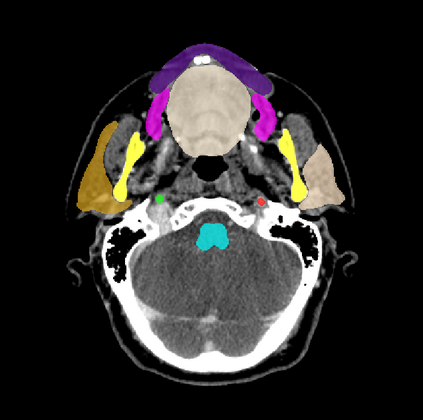

Organ at risk (OAR) segmentation is a critical process in radiotherapy treatment planning such as head and neck tumors. Nevertheless, in clinical practice, radiation oncologists predominantly perform OAR segmentations manually on CT scans. This manual process is highly time-consuming and expensive, limiting the number of patients who can receive timely radiotherapy. Additionally, CT scans offer lower soft-tissue contrast compared to MRI. Despite MRI providing superior soft-tissue visualization, its time-consuming nature makes it infeasible for real-time treatment planning. To address these challenges, we propose a method called SegReg, which utilizes Elastic Symmetric Normalization for registering MRI to perform OAR segmentation. SegReg outperforms the CT-only baseline by 16.78% in mDSC and 18.77% in mIoU, showing that it effectively combines the geometric accuracy of CT with the superior soft-tissue contrast of MRI, making accurate automated OAR segmentation for clinical practice become possible. See project website https://steve-zeyu-zhang.github.io/SegReg